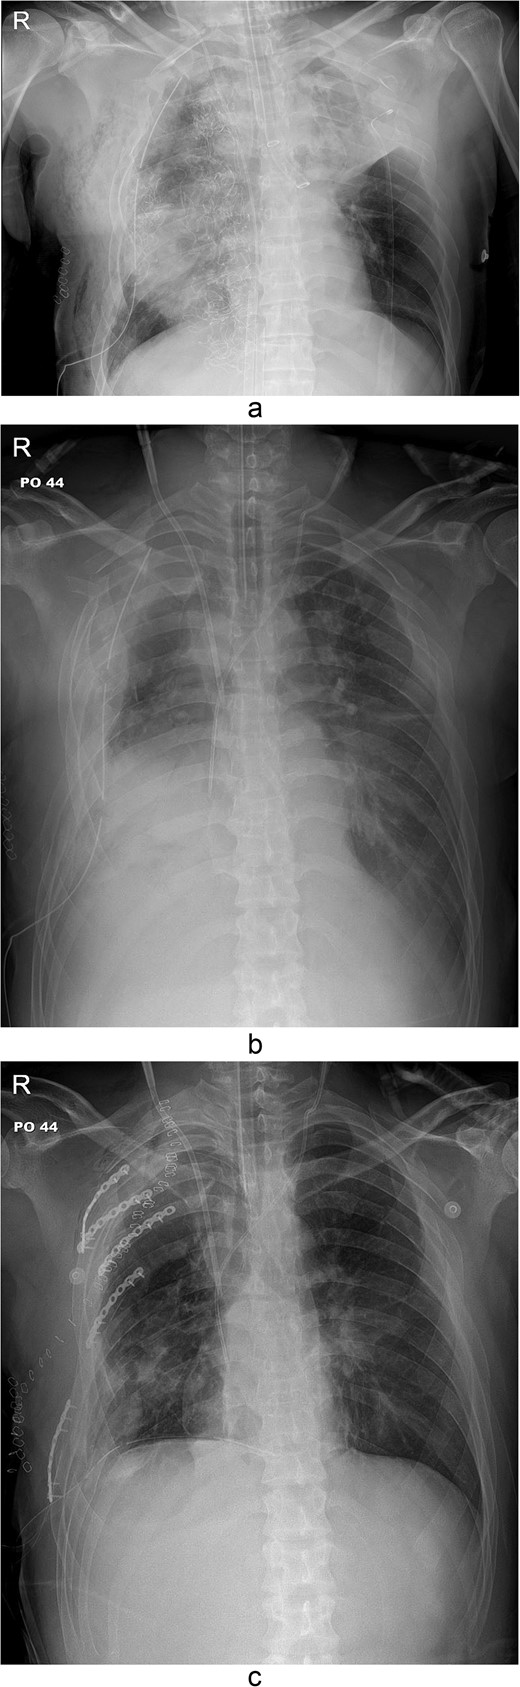

A 31-year-old unconscious male was in an unwitnessed accident when a car hit the motorcycle he was driving. A rescue team transported him to the emergency department. Clinical examination revealed hypoxia with SpO2 at 85%, tachycardia at 126 bpm, hypotension of 69/58 mmHg, and hypothermia at 35.8°C. Initial arterial blood gas analysis (ABGA), pH, PaO2, and pCO2 were 6.92, 49, and 58, respectively. Chest X-ray showed right hemopneumothorax, mediastinal shifting, and multiple bilateral rib fractures (Fig. 1). A right-side closed thoracostomy was performed. The chest drainage of 1 L was bloody. Chest computed tomography (CT) showed fractures in the right ribs 1 to 9 and left ribs 1 to 7, as well as lung contusions, multiple lung lacerations, right hemopneumothorax, and active hemorrhage in the right upper and lower lung lobes (Fig. 2). Brain and abdominopelvic CT showed no organ injury. An emergency thoracotomy was ordered.

Simple radiographs obtained after each operation. (a) Radiograph after the first operation. Gauze, which is visible as a wavy white line, was packed in the right thoracic cavity. Multifocal opacity was seen in the right lung, and there was left upper lung atelectasis. ECMO catheters were placed in the IVC. (b) Radiograph following the second operation. The right ribcage is narrowed due to displaced fractured ribs. (c) Radiograph after the third operation. Five plates were applied to the fractured ribs.